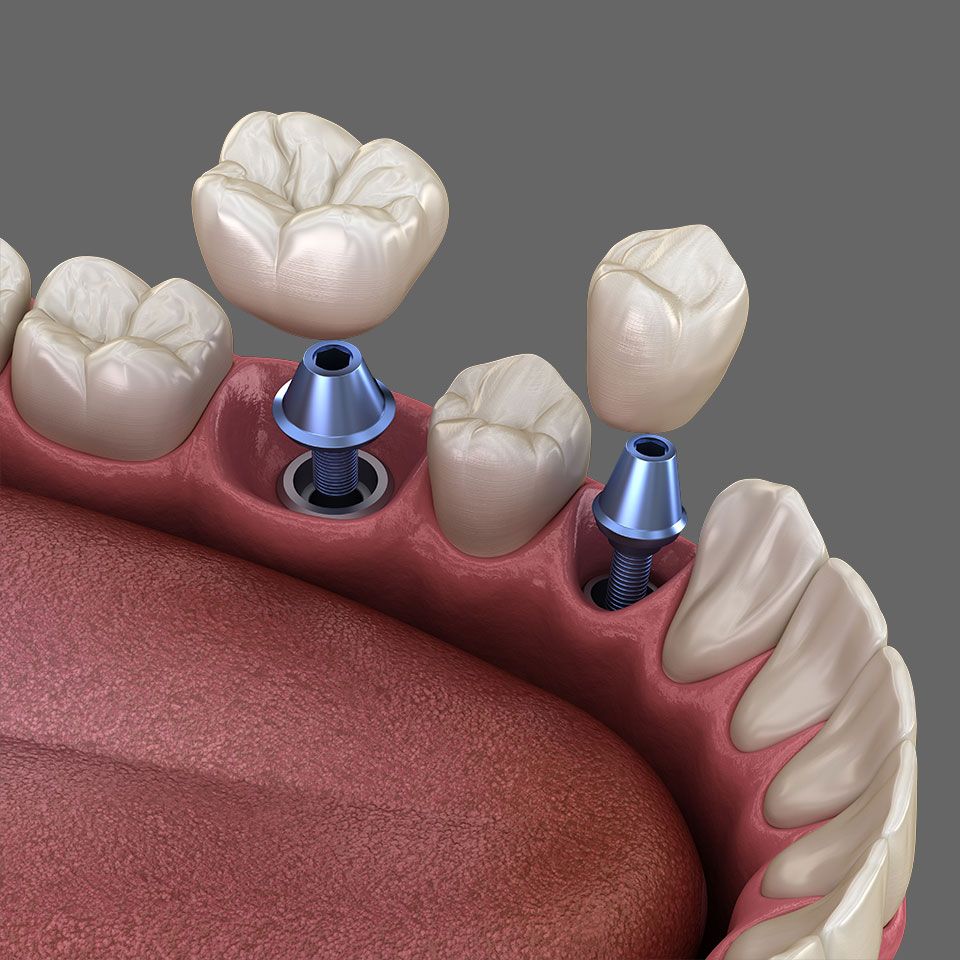

Um einzelne Zähne zu ersetzen und Lücken zu schließen, sind Implantate heute die erste Wahl. Der Kieferknochen bleibt intakt und die Nachbarzähne werden geschont.

Diese künstlichen Zahnwurzeln sind zumeist aus Titan – einem gut verträglichen (biokompatiblen) Material. Sie werden in den Kieferknochen eingesetzt, wo sie mit dem Knochen fest verwachsen. So können sie einer Einzelkrone, Brücke oder Zahnprothese stabilen Halt verleihen.

Lücken-Versorgung mit Einzelimplantaten